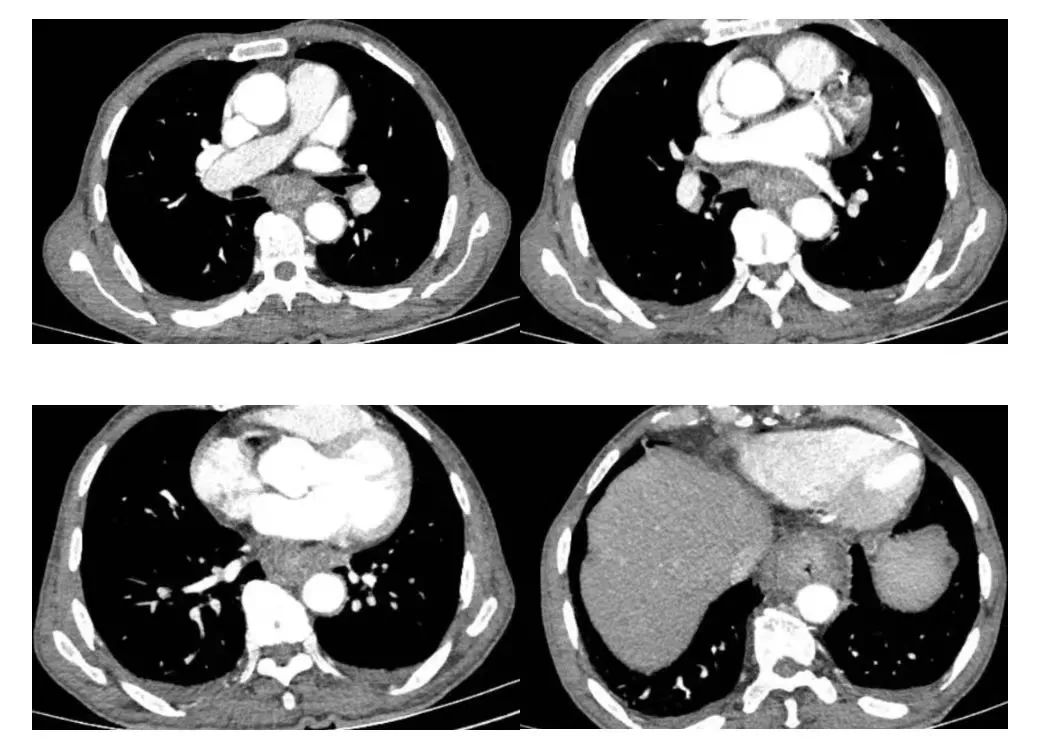

胸部增强CT:患者食管中下段管壁、贲门处胃壁明显增厚

医生进一步询问病史,发现患者有进行性吞咽困难1月余,伴有体重减轻,乏力等症状。胸外科主任李建新在分析病情后考虑食管中下段癌累及贲门胃底可能,患者合并白血病,伴有贫血、血小板减少,营养不良性低蛋白血症,脾功能亢进,有化疗禁忌,若不及时手术干预,情况必然恶化。